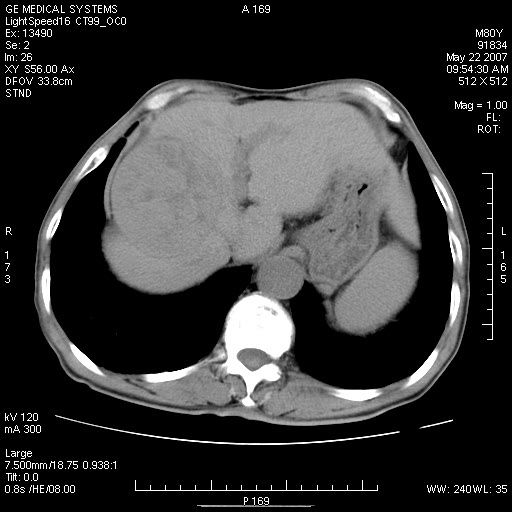

标题: CT8346:男,80岁。血尿,肝脏,膀胱占位,是否为肝转移?

男,80岁。血尿,无腹部不适病史。

肝脏病变:

看看平扫的,再看看增强动脉期的,怎么也不是囊肿。

肝脏内病灶有假包膜,增强扫描动脉期有动静脉瘘,有快进快出特点,考虑原发性肝癌。病灶内有裂隙样低密度影,以纤维板层样细胞癌可能性大。膀胱左侧乳头状占位,增强呈明显强化,左侧盆腔内有肿大淋巴结,结合有血尿病史,考虑膀胱癌左侧盆腔淋巴结转移。